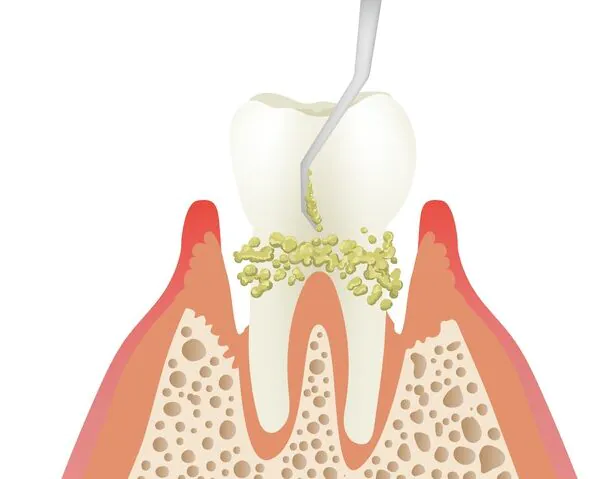

歯周病の主な原因はプラークと呼ばれる歯垢です。プラークは歯と歯ぐきの間に形成され、乳白色の粘性のある物で、中には歯周病やむし歯の原因となる細菌が集まっています。

1mgのプラークには約10億もの細菌が含まれているとされています。時間の経過とともに、プラークはバイオフィルムとして強固な集合体へと変化します。

このバイオフィルムは唾液の殺菌作用を避け、歯周病やむし歯の進行を促進します。歯垢の効果的な予防と管理は、歯科衛生の基本であり、日常的な歯磨きや定期的な歯科検診が重要です。